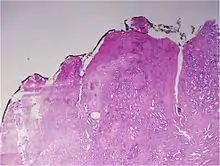

Gleason Pattern 3. H&E stain.

• Pattern 3 - The tissue still has recognizable glands, but the cells are darker. At high magnification, some of these cells have left the glands and are beginning to invade the surrounding tissue or having an infiltrative pattern. This corresponds to a moderately differentiated carcinoma.

Gleason 3

Gleason 3 is a clearly infiltrative neoplasm, with extension into adjacent healthy prostate tissue. The glands alternate in size and shape, and are often long/angular. They are usually small/micro-glandular in comparison to Gleason 1 or 2 grades. However, some may be medium to large in size. The small glands of Gleason 3, in comparison to the small and poorly defined glands of pattern 4, are distinct glandular units. Mentally you could draw a circle around each of the glandular units in Gleason 3.[4][7]